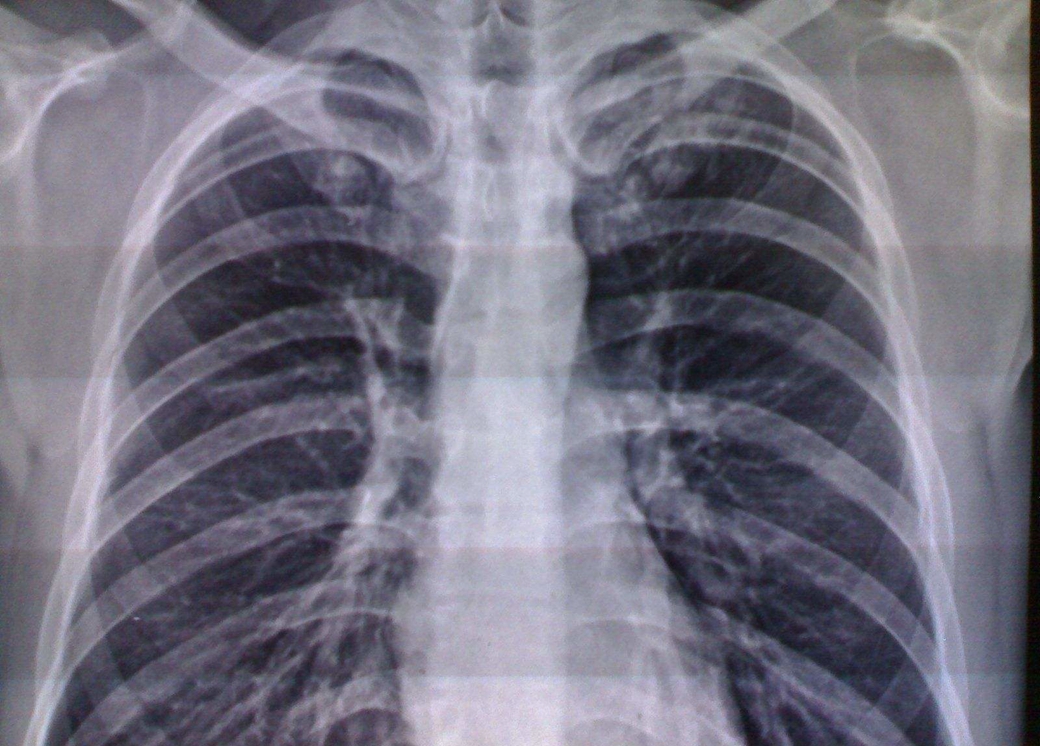

弥漫性阻塞性肺气肿:①胸廓呈桶状,前后径增宽,肋走行变平,肋间隙增宽,横膈较低平,膈活动度减弱。②两肺野透明度见增加,呼、吸时其改变不大,可见单或多发肺大,肺纹理可见稀疏变细,中外带纹理可消失,肺门处肺纹理可增粗,伴有肺间质纤维化时,肺纹理不减少而增强,并可呈网状或蜂窝状。③心景居中而狭长呈垂滴状。